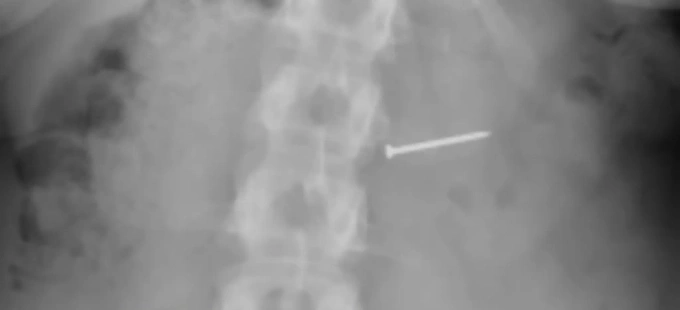

Buckley sau đó đến bệnh viện để chụp X-quang để chắc chắn thứ mình nghẹn có đúng là quả hồ đào hay không nhưng không phải. “Đó là một cái đinh. Vậy là tôi đã nuốt phải một cái đinh”, cô nói.

Hình ảnh chụp X quang của Brandy Buckley. Ảnh: NYPost